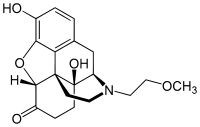

Several semi-synthetic opioids were developed in Germany in the 1910s. The first, oxymorphone, was synthesized from thebaine, an opioid alkaloid in opium poppies, in 1914.[228] Next, Martin Freund and Edmund Speyer developed oxycodone, also from thebaine, at the University of Frankfurt in 1916.[229] In 1920, hydrocodone was prepared by Carl Mannich and Helene Löwenheim, deriving it from codeine. In 1924, hydromorphone was synthesized by adding hydrogen to morphine. Etorphine was synthesized in 1960, from the oripavine in opium poppy straw. Buprenorphine was discovered in 1972.[228]

Opium alkaloids and derivatives

Phenanthrenes naturally occurring in (opium):

Semi-synthetic alkaloid derivatives

- Buprenorphine

- Etorphine

- Hydrocodone

- Hydromorphone

- Oxycodone (sold as OxyContin)

- Oxymorphone